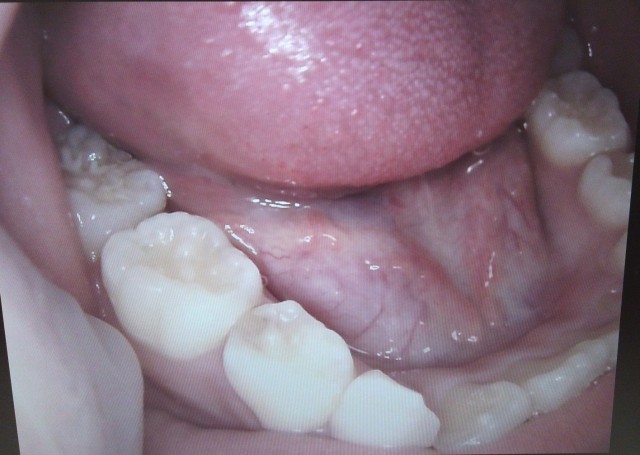

舌下(ぜっか)部、口底部に生じた貯留嚢胞(ちょりゅうのうほう)をいいます。

透明感のある半球状のふくらみで、ガマガエルののどに似ているのでがま腫と呼びます。

口底部の粘膜下に片側性に発生し、徐々に大きくなり、

嚥下(えんげ)時などの舌の運動を損なうようになります。